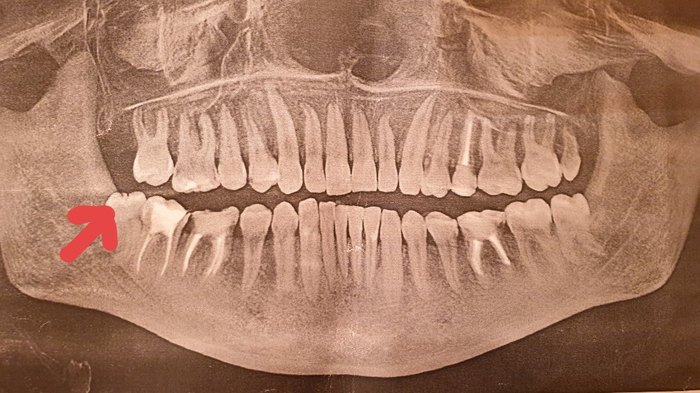

Заблаговременно, я героически удалила 3 8-ки. (Это вынужденная мера. Особенно, когда они не прорезалились до конца. В мои-то 27 не все 8ка вылезли!). Далее адский снимок мой челюсти. Стрелочками показаны 8ки. Корни у этих нычек ужасные. Кривые, закорюченые, ужас.

Хирург с асисстенкой за 2 недели сделали невозможное. Оказалось,что 1 восьмерки вверху у меня нет (стандартная аномалия. Нет корней и все), вторую 8ку сверху удалили в день посещения, а 2 нижних удаляли с разбегом в неделю, чтобы не занести инфекцию и дать организму восстановиться.